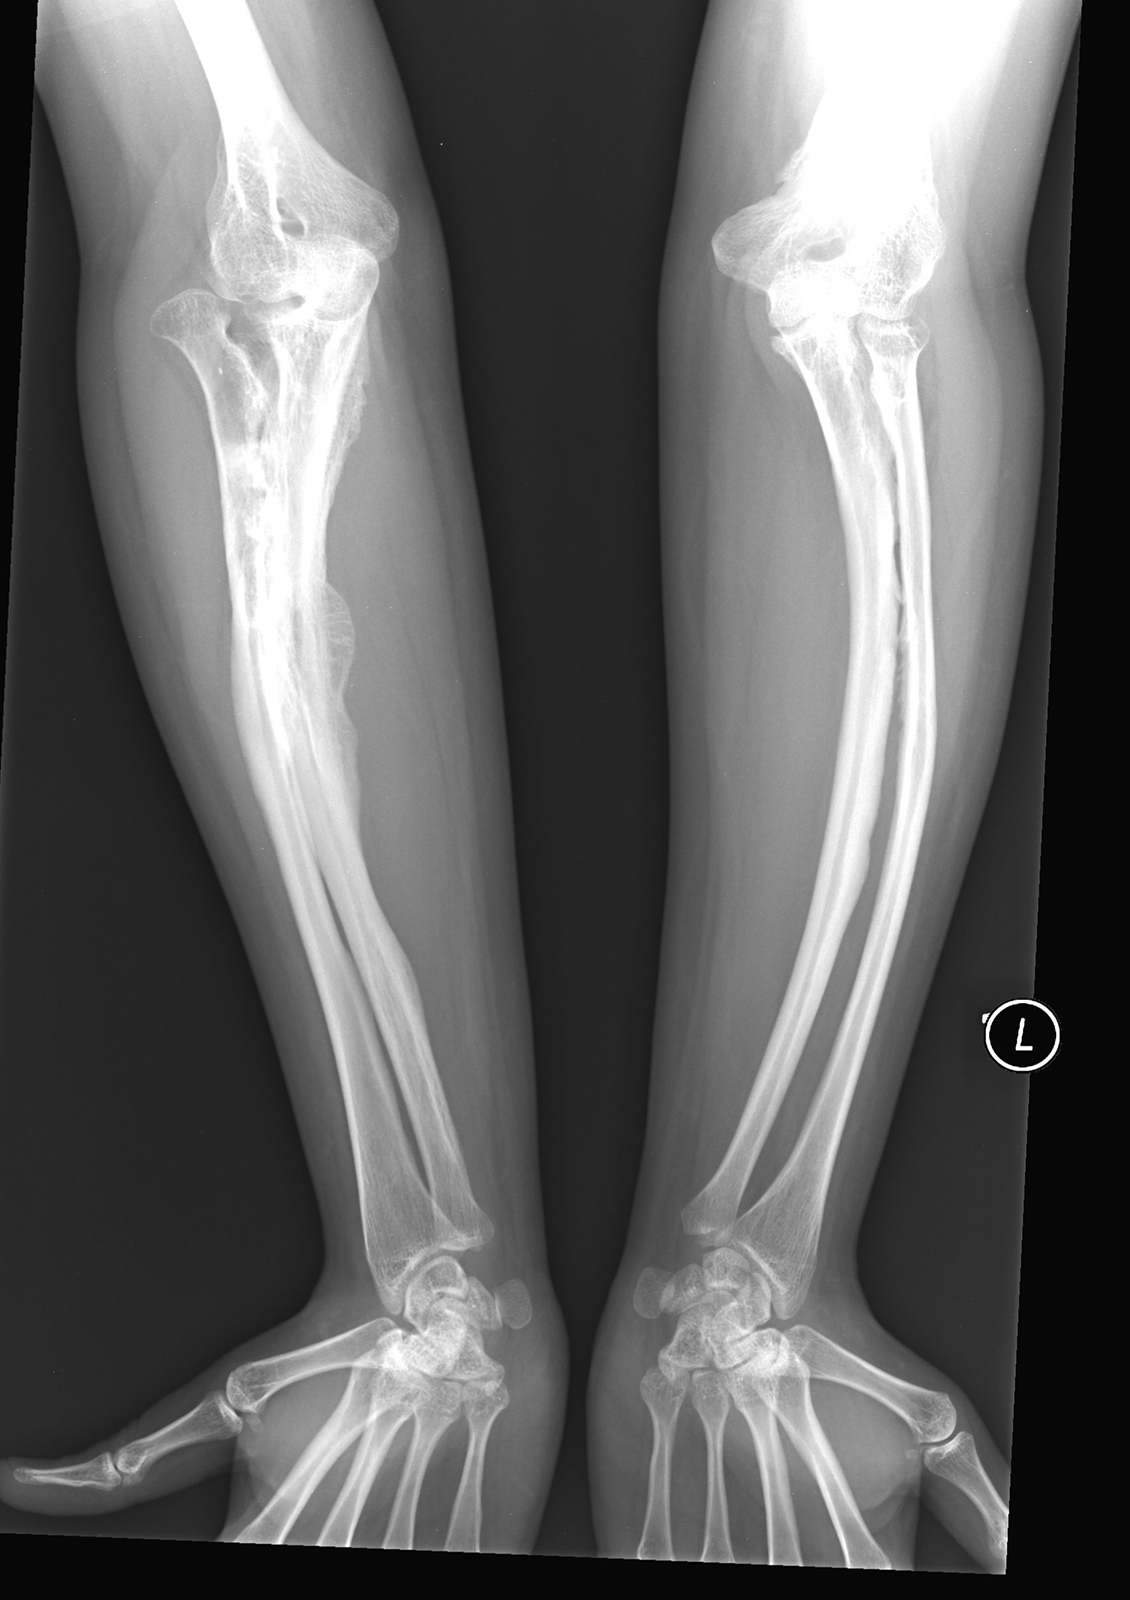

Osteogenesis Imperfecta (OI) is a genetic condition present from birth.

Its primary feature is fractures usually caused by minimal impact

Fractures can occur with minimal force – this varies from child to child.

Bones may have an altered shape, for example, they may be shortened or bowed.